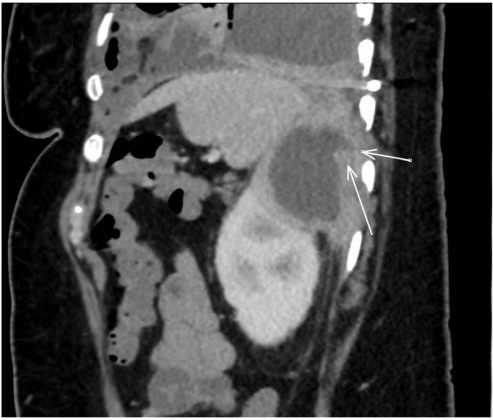

在有房颤的情况下,用组织纤溶酶原激活剂(tPA)和脱氧核糖核酸酶(DNAse)行胸膜腔内溶栓治疗72小时。纤溶治疗后无明显改善,患者被带到手术室进行大口径胸导管放置和电视胸腔镜手术(VATS)剥离左内脏胸膜。胸膜液培养出奇异变形杆菌(图1),因此患者接受了进一步的影像学检查,以确定主要来源。腹部/骨盆的计算机断层扫描(CT)显示左肾上极有一个复杂的囊性病变,与同侧横膈膜相通(图2,3)。尿液分析不明显。在脓肿内放置引流管,囊肿液培养也显示奇异变形杆菌阳性。

图2. 计算机断层扫描结果显示患者腹部的矢状面,白色箭头显示肾囊肿向后延伸至膈肌